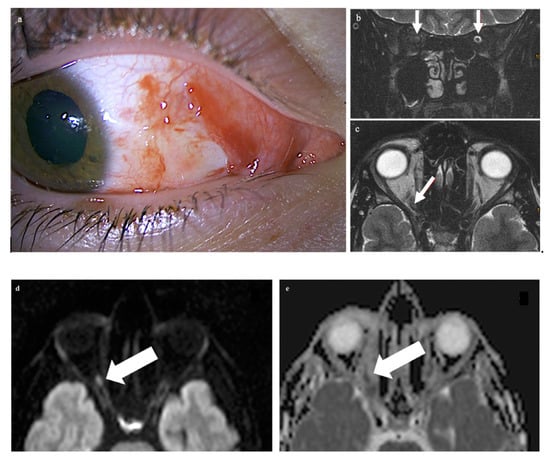

A 21-year-old male patient presented with vision loss in his right eye after trauma. He had injured himself with a metal gardening device and suffered parabulbar penetration of a metal rod into the orbit with only minimal ocular trauma. The metal rod was thin, but with a blunt end; it directly hit and tore into the orbit. Examination of the right eye revealed a superficial conjunctival wound nasally and a dilated pupil (Figure 1a). Ophthalmological examination of the left eye was normal. The globe was not injured. The cornea, lens, retina, and optic nerve head appeared normal upon ophthalmologic examination. Functional ocular examination, however, showed no light perception and a relative afferent pupillary defect.

Examination of the right eye revealed a superficial conjunctival wound nasally and a dilated pupil (a). On the MRI scan, there is loss of the subarachnoid space in the right optic nerve (arrows in panel (b): the subarachnoid space of the left optic nerve is normal). The respective transverse T2-weighted image shows a central signal increase in the optic nerve (arrow in (c)). On the diffusion-weighted imaging, a punctuate signal increase in the optic nerve in the same location is seen (arrow in (d)); the corresponding ADC map shows signal loss in the same location (arrow in (e)). The globe as well as the left eye and orbit are unchanged, while there is a diffuse signal increase (arrows) in the right retrobulbar space nasally (f,g).

CT of the facial skull showed neither fractures nor foreign bodies, metallic or otherwise (Somatom Excite, Siemens Healthineers, Erlangen, Germany). The optic canal was normal. MR imaging was performed 4 hours after the trauma on a 1.5 T imager (Symphony, Siemens Healthineers, Erlangen, Germany) with a standard head coil. Plain T1w spin-echo images in the transverse orientation (TR 500 ms, TE 8.8 ms) and plain T2w turbo spin-echo transverse and coronal images with and without fat saturation (TR 4.000 ms and TE 128 ms) by prepulse were obtained in a 2 mm slice thickness. For DWI and ADC maps, a transverse orientation was chosen (5 mm slice thickness, TR 2500, TE 80 ms, and b-value of 1.000 s/mm2). Imaging demonstrated on coronary T2-weighted fat-saturated MRI loss of the subarachnoid space in the right optic nerve (white arrows in panel b: the subarachnoid space of the left optic nerve is normal) while the respective transverse T2-weighted image revealed slight optic nerve distention with a central signal increase (white arrow in c) right frontally from the optic canal. Diffusion-weighted imaging showed a punctuate signal increase in the optic nerve in the same location (d); the corresponding ADC map had signal loss in the same location (e). The globe was unchanged, while the retrobulbar space showed a diffuse signal increase nasally (f,g). The left eye and orbit were normal.